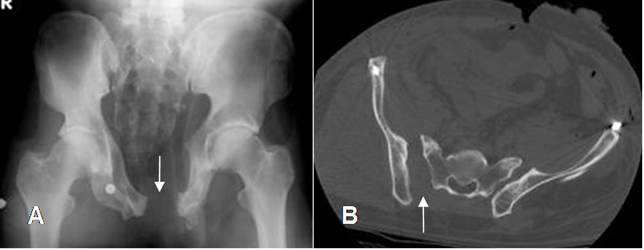

Fig 42 A. Trauma de pelvis. Compresión AP.

A: Rx AP y B: TAC axial. Luxofractura de la sínfisis púbica del lado izquierdo.

Fig 42 B. Diastasis.

A: Rx AP y B: TAC axial. Diastasis de la sínfisis púbica, conservándose íntegras las articulaciones sacroiliacas. Hay fractura vertical del sacro, sobre la línea media.

Fig 42 C. Diastasis.

A: Rx AP. Diastasis de la sínfisis púbica.

B: TAC axial. Diastasis asociada de la sacroiliaca derecha.